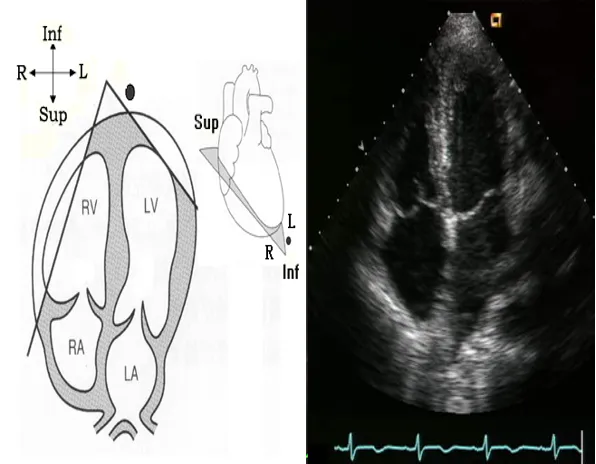

心尖四腔心切面

探头位置:探头置于心尖搏动点处;探头指向右胸锁关节。

观察内容

● 瓣膜活动:二尖瓣及三尖瓣形态结构与活动。

● 腔室大小:左房,左室,右房,右室。

● 室壁运动:左室壁的侧壁和后室间隔。

● 室壁厚度:左室壁的侧壁和后室间隔。

● 结构的连续:房间隔和室间隔。

● Simpson心功能的测定。